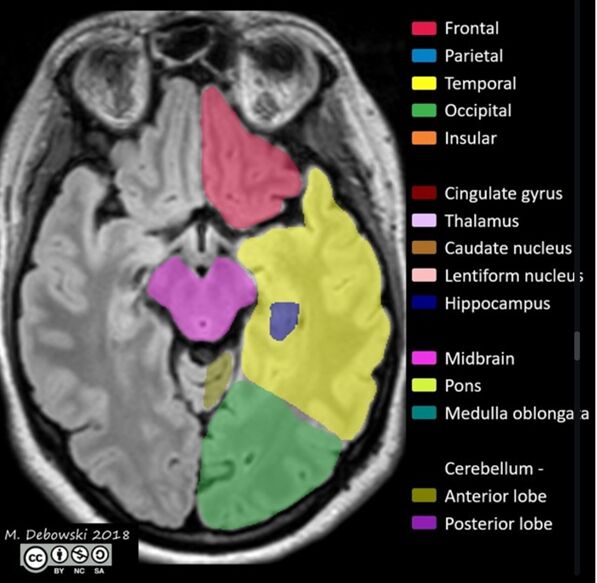

https://radiopaedia.org/cases/brain-lobes-annotated-mri-1#image-44335122